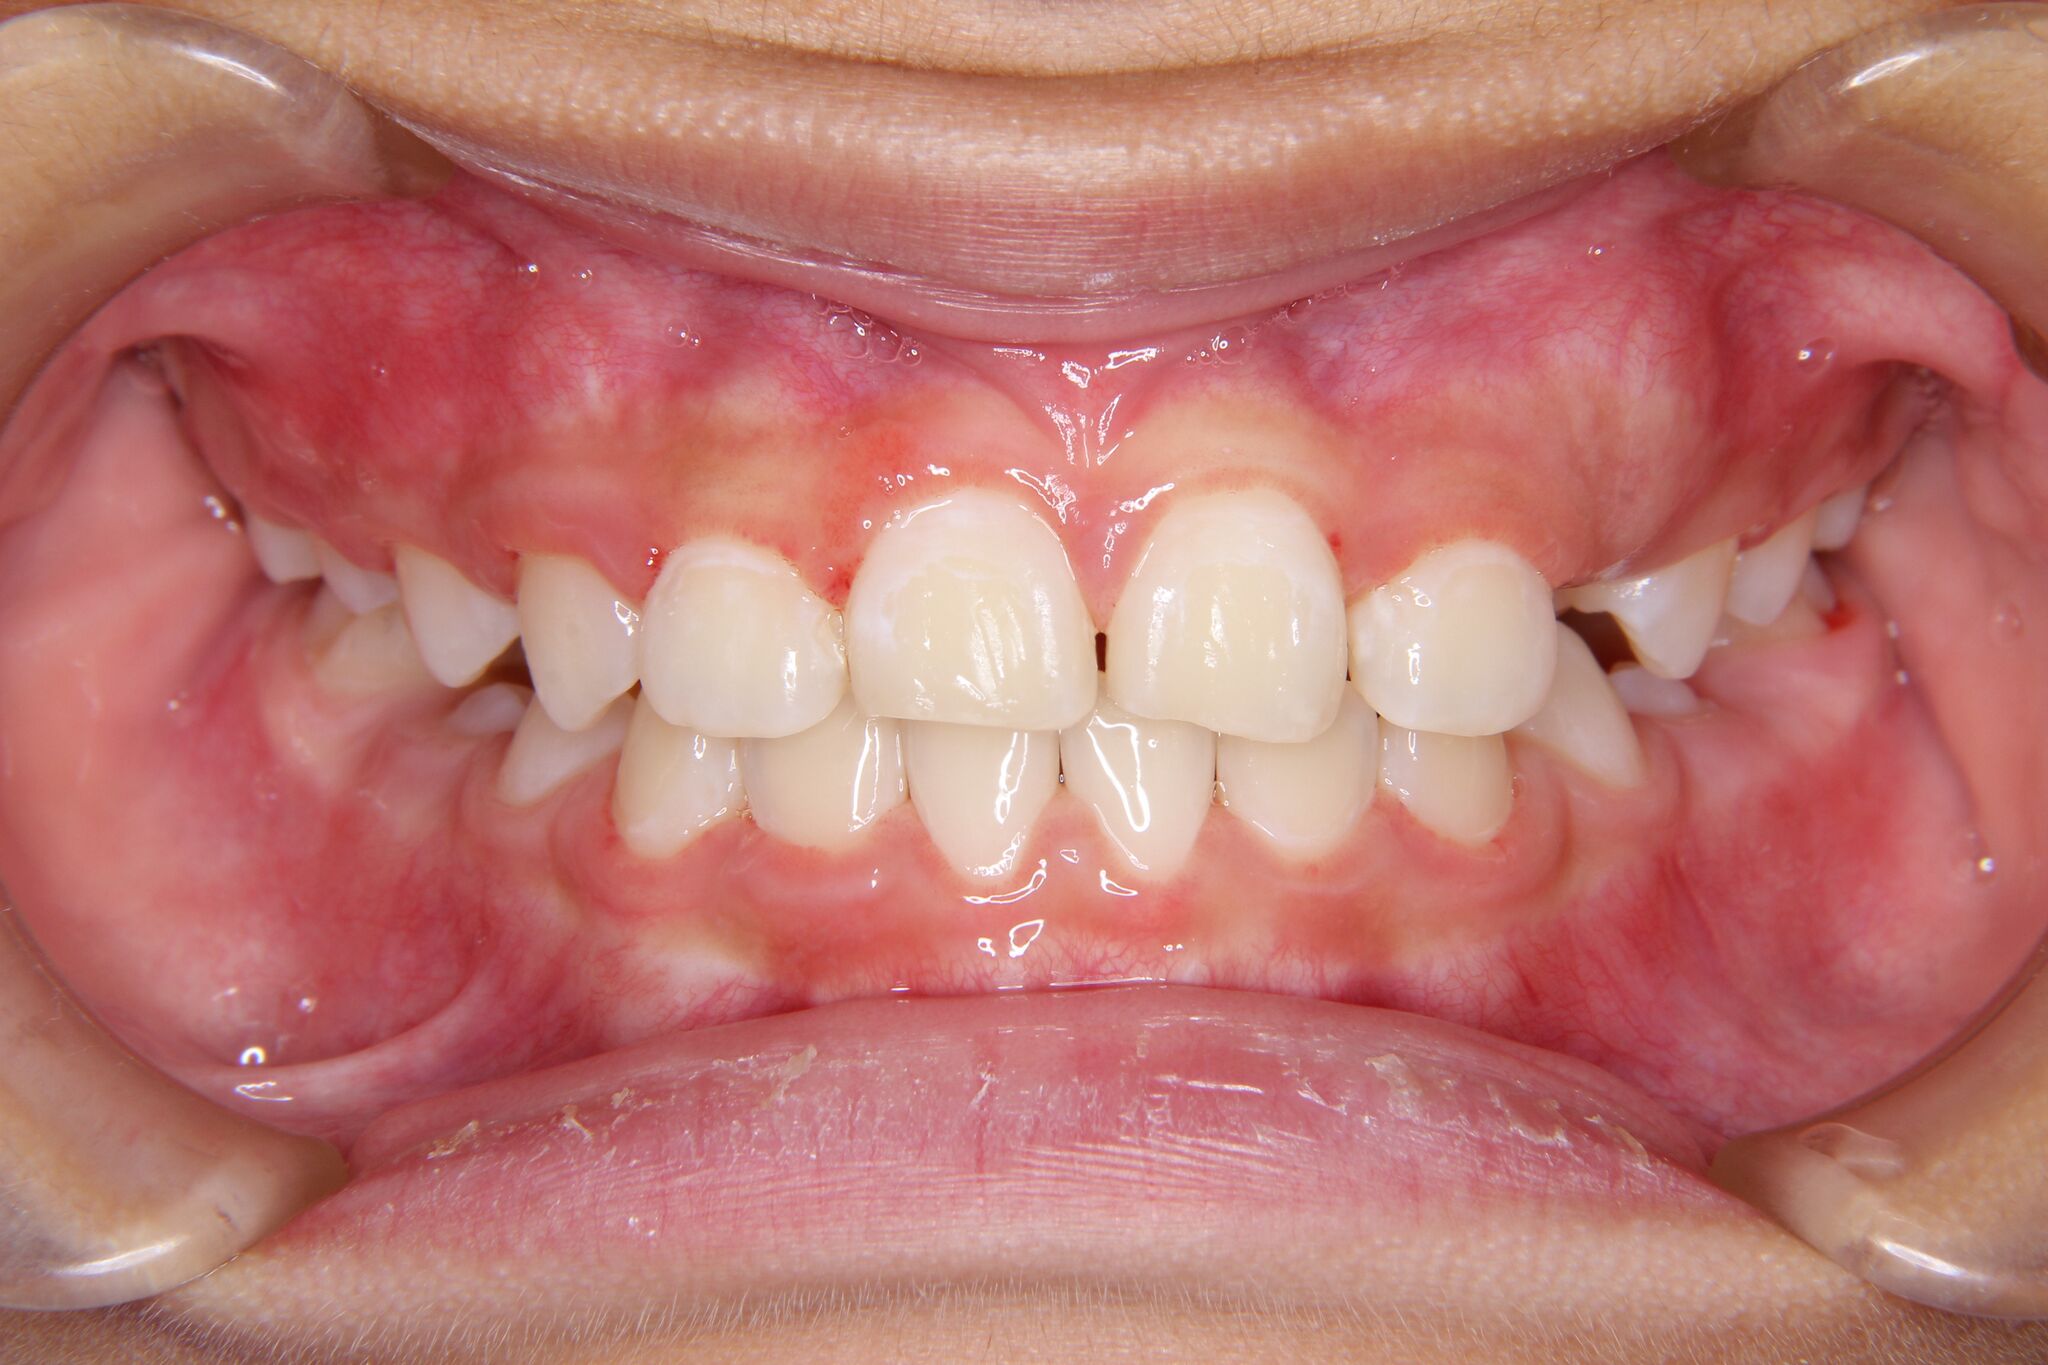

- 治療前 治療後

上下顎の歯列弓(歯のアーチ)を拡大(広げること)をしました。

アーチを広げることで、下の前歯を内側に移動させるスペースが出来ますし、上顎のアーチを広げることで、下顎が正しい位置に収まる受け皿をしっかり作っていきます。

今回は、プレートタイプの拡大床を使用しました。

拡大床によるスペースコントロール後、ワイヤーを装着。歯のがたがたを治療していきました。ワイヤーの装着期間は約半年ほどでした。小児矯正は、2×4装置といって、前歯4本と、六歳臼歯にブラケットを装着し、ワイヤーを部分的にセットする方法がよく用いられます。

顎のずれは、歯の早期接触部位を改善することで、自然に偏位が改善されてきました。

今後は、永久歯完成まで経過観察を行い、永久歯が全て生えそろった段階で、一度再評価をしていきます。その後、再分析、再診断を行い、第二期治療(成人矯正治療)を行うか患者様と相談します。